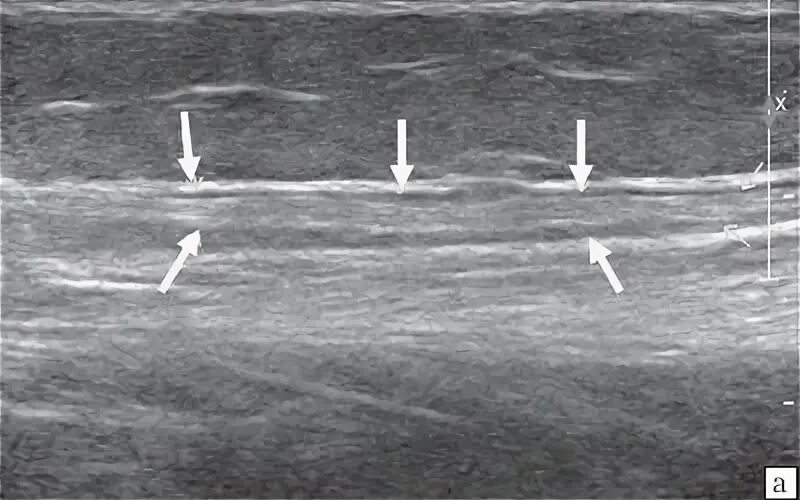

Узи нервов сделать в москве